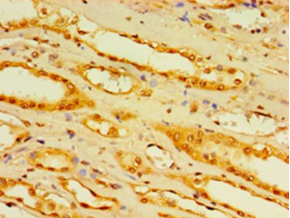

DescriptionDCP2 Polyclonal Antibody. Unconjugated. Raised in: Rabbit.

ApplicationELISA, IHC; Recommended dilution: IHC:1:20-1:200